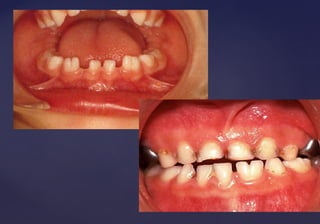

GEMINACIÓNGEMINACIÓN::

 Formación de dientesFormación de dientes

gemelos.gemelos.

 Generalmente dosGeneralmente dos

supernumerarios o unsupernumerarios o un

supernumerario con otrosupernumerario con otro

diente de la serie normal.diente de la serie normal.

 Causa: División del germenCausa: División del germen

dentario anormalmentedentario anormalmente

grande, o a un sinodontismogrande, o a un sinodontismo

(unión con gérmenes de(unión con gérmenes de

dientes vecinos)dientes vecinos)

 Frecuentes en ICS y en ILI;Frecuentes en ICS y en ILI;

dientes inftantiles.dientes inftantiles.

• Presentan continuidad de las

cámaras pulpares y de la dentina.

• Radiográficamente se observan dos

coronas conformadas con un canal

radicular.

FusiónFusión

 Unión de dos dientes de la serie normal, mediante la dentina,Unión de dos dientes de la serie normal, mediante la dentina,

independientemente de la pulpa y del esmalte.independientemente de la pulpa y del esmalte.

 Se cree que es causada por la presión o fuerza durante el desarrollo de laSe cree que es causada por la presión o fuerza durante el desarrollo de la

raíz adyacente.raíz adyacente.

 Frecuente entre incisivos central y lateral y lateral y canino de dientesFrecuente entre incisivos central y lateral y lateral y canino de dientes

temporarios.temporarios.

 Mas frecuentes en la zona mandibular anterior.Mas frecuentes en la zona mandibular anterior.